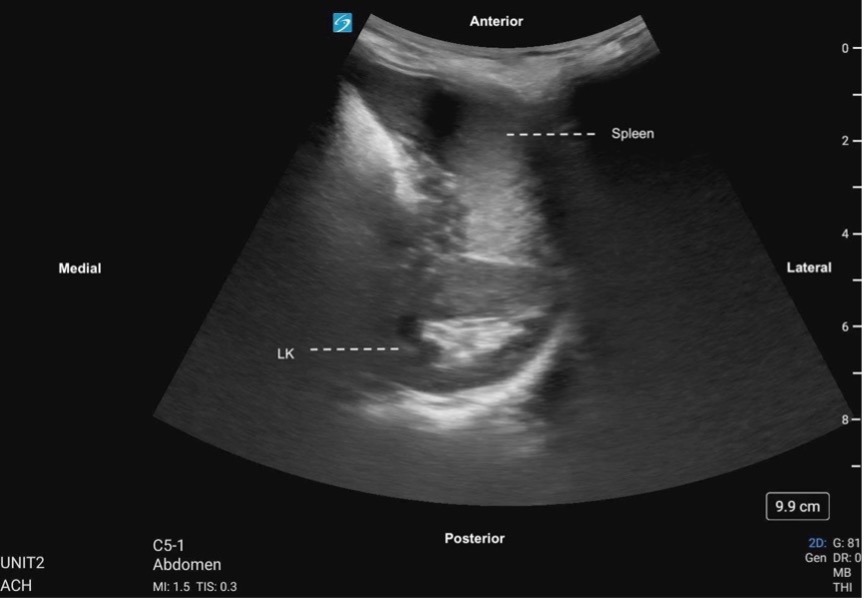

Subcostal Four Chamber

The subxiphoid 4 Chamber view can be used to assess ventricular function, particularly during emergent situations, when access to the other windows is limited.

The left ventricle is seen in the far field with the septal and lateral walls in view. The RV is seen more anteriorly.

Figure 25. Subxiphoid 4 chamber with the LV walls labeled